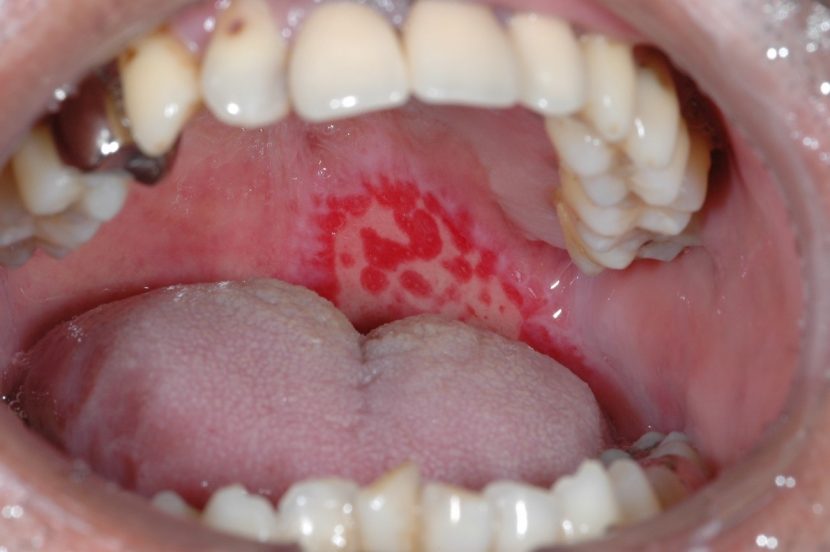

ニコチン性口内炎 舌 (461 無料写真)

ニコチン性口内炎 舌